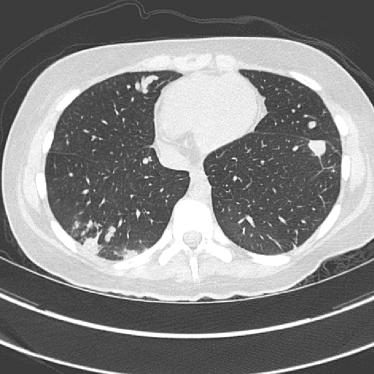

To evaluate image quality, we first tested the performance of JENG on a standard CT phantom, CT ACR 464 phantom 35. Then we tested JENG on 5 clinical thoracic datasets and 3 abdominal datasets. The ACR 464 phantom contains four modules in total, with each module 40 mm in depth and 200 mm in diameter. The first module has 4 different inserts to test CT number fidelity. In addition, the module contains a series of wires for cross-plane resolution evaluation, shown as white horizontal bars near the center in Fig. 9(a), and are visible in 0.5 mm z-axis increments. The second module tests low contrast resolution, but is not used in this paper. The third module, shown in Fig. 9(b), is a uniform cylinder of water-equivalent material of 0 Hounsfield units (HU), and we used this module to quantitatively measure image noise profile and in-plane resolution. The fourth module consists of resolution bars of various spatial frequencies for analysis on high contrast resolution. To scan the phantom, the scanner setup used dual sources with 2 focal spots at each source. In addition, the projections were acquired using the same protocol for clinical thoracic scans with 100 KV, a nominal tube current of 718 mA and a high helical pitch of 2.8. For all experiments, we compared JENG against the state-of-the-art Siemens ADMIRE, reconstructed with a BL-64 soft tissue sharp kernel, and we define ADMIRE as the clinical standard hybrid IR method for the rest of the paper.

Finally, we tested the qualitative clinical results of JENG on 5 thoracic and 3 abdominal scan datasets in terms of spatial resolution, artifacts, image noise and low-contrast detectability. All clinical scans were retrospective and were acquired during routine clinical practice at a major children’s hospital in the United States. All thoracic scans used the same settings as in the ACR phantom scans, except that the tube current was modulated differently for each patient based on their body thickness, weight, and age. The abdominal scans, however, had a reduced helical pitch at 0.6 to improve low contrast lesion detectability. For all clinical images in this paper, the clinical standard hybrid IR used a soft tissue high-contrast kernel for reconstructions and we compared the image noise and artifacts of JENG and the clinical standard hybrid IR after we matched their spatial resolution.

Figure 14: Qualitative clinical results from a thoracic CT staging dataset for a 12-year-old with osteosarcoma with pulmonary metastases. The clinical standard hybrid IR is shown on the left and JENG is on the right. (a) The clinical standard hybrid IR in lung window with a window center of -600 HU and a window width of 1500 HU. (b) JENG at a resolution comparable to the clinical standard, but with less noise and fewer artifacts. (c) The clinical standard hybrid IR in soft tissue window with a window center of 55 HU and a window width of 440 HU. A metastatic lung cancer nodule can be found in the left upper lobe. (d) JENG in soft tissue window at a comparable resolution, but with less noise and fewer artifacts. Note that JENG is not fully corrected for beam hardening artifacts.